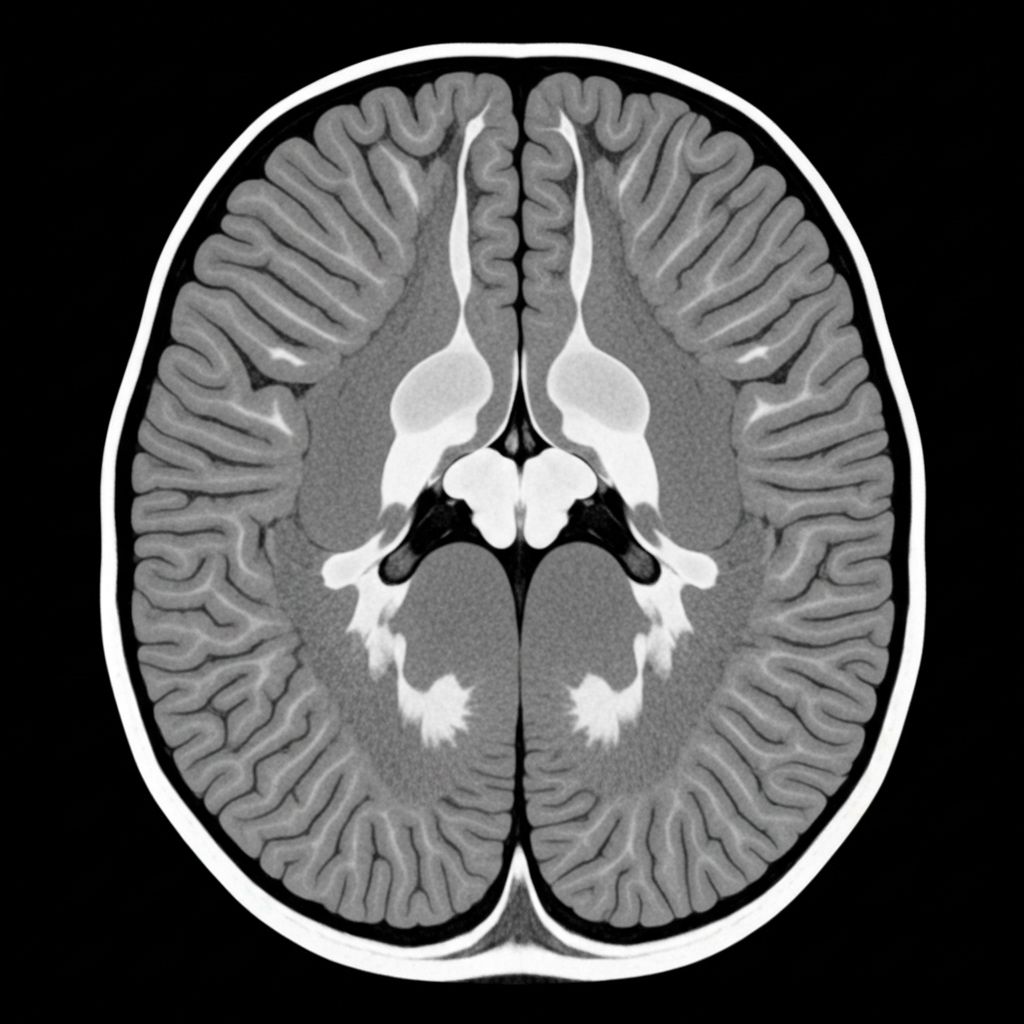

T1-weighted MRI with contrast showing enhancing lesion with surrounding edema, consistent with high-grade glioma characteristics.

Primary hypothesis: High-grade glioma (78% confidence)

Enhancing lesion with surrounding edema signature

Requires neuroradiology consultation for staging